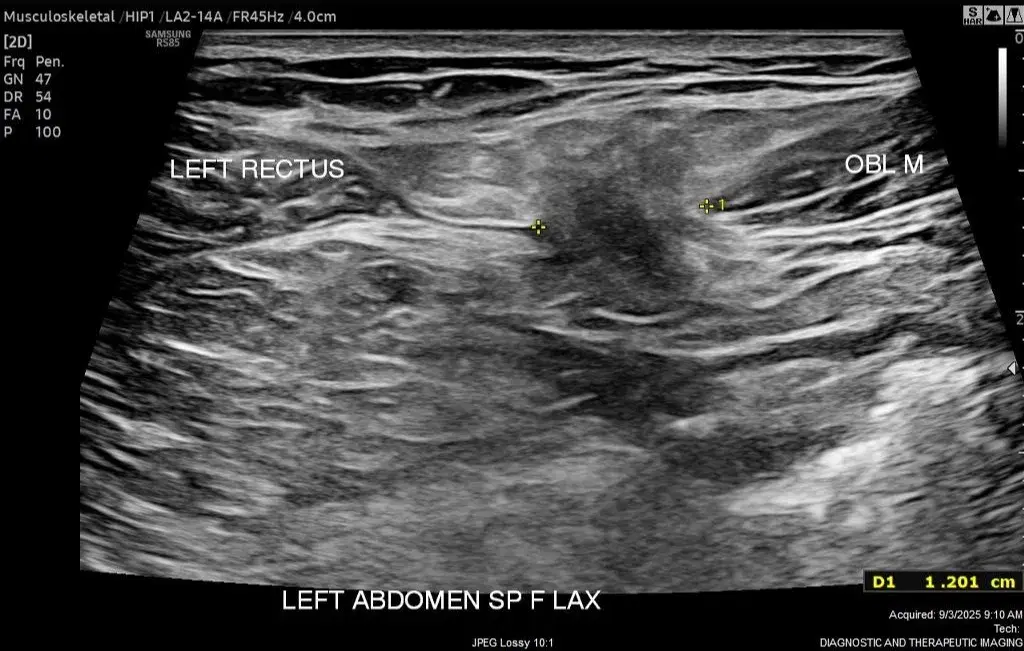

SPIGELIAN - DYNAMICS

Musculoskeletal

Hip pain from a Spigelian hernia